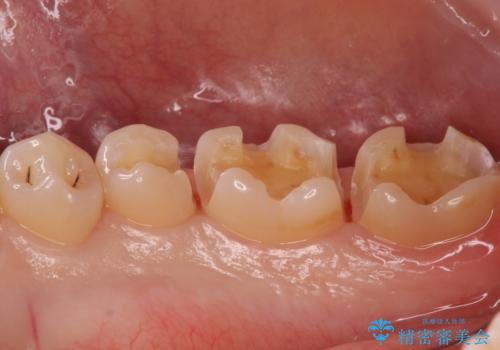

- 銀の詰め物を白くしたいとのことで来院されました。

特に大きな虫歯もなかったため、セラミックインレーで修復処置をしていきます。

写真でもレントゲン画像でも確認できるように、段差がなく適合の良い詰め物を装着することができました。